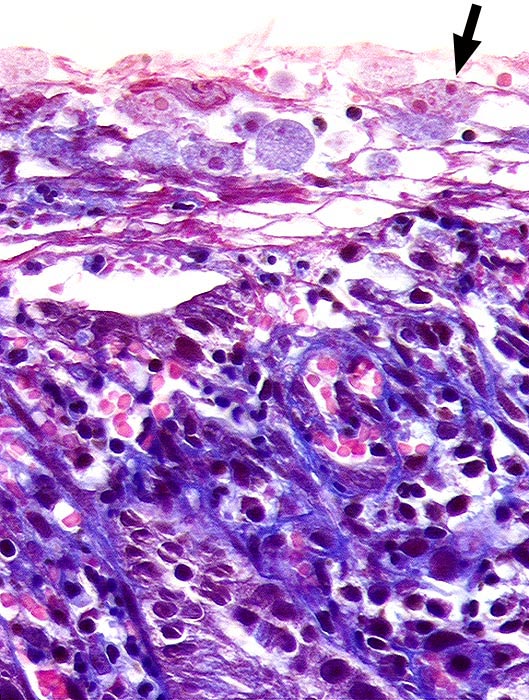

Amöben

Entzündung infektiös

Kolon

Auf dem Oberflächenepithel liegen zahlreiche Amöben mit feinkörnigem hellblauem Zytoplasma. Ein Teil davon mit phagozytierten Erythrozyten.